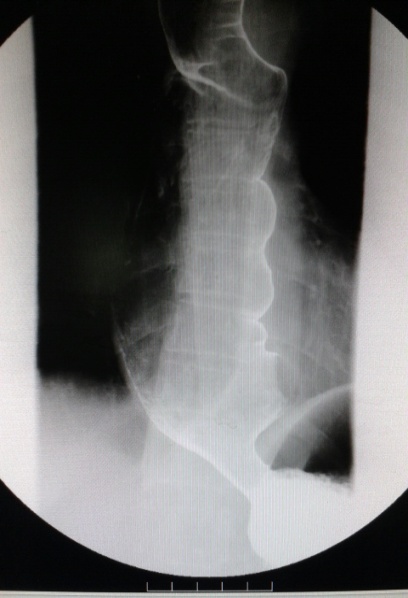

术前(食管中下段管腔明显扩张,贲门呈鸟嘴样狭窄)

POEM术后(贲门开放良好)